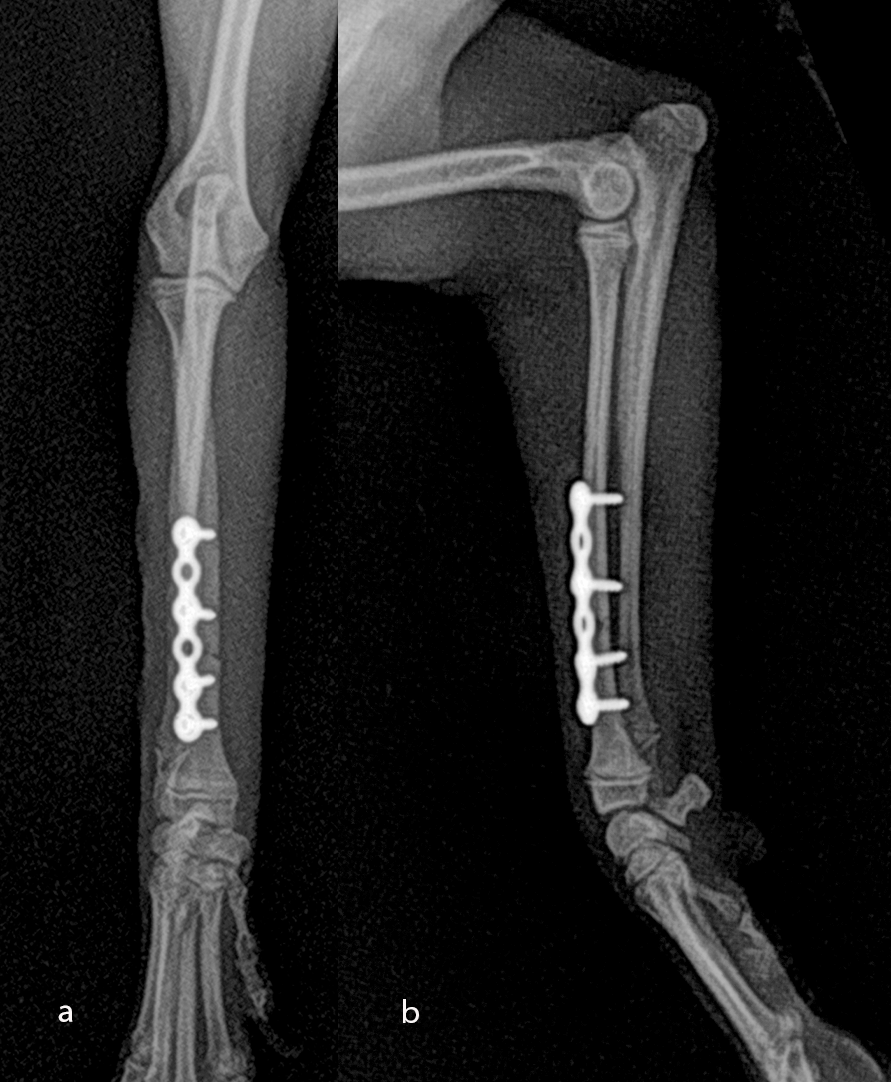

An open but do-not-touch approach was performed, and the plate was fixed with one proximal and one distal cortex screws and one proximal and one distal locking screws (Fig 8). After 1 month the fracture of the radius was healed, and the dog had a complete functional recovery (Fig 9).